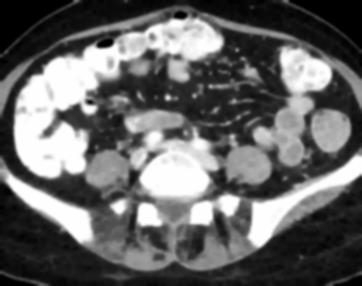

Due to the constraints of the imaging device and high cost in operation time, computer tomography (CT) scans are usually acquired with low intra-slice resolution. Improving the intra-slice resolution is beneficial to the disease diagnosis for both human experts and computer-aided systems. To this end, this paper builds a novel medical slice synthesis to increase the between-slice resolution. Considering that the ground-truth intermediate medical slices are always absent in clinical practice, we introduce the incremental cross-view mutual distillation strategy to accomplish this task in the self-supervised learning manner. Specifically, we model this problem from three different views: slice-wise interpolation from axial view and pixel-wise interpolation from coronal and sagittal views. Under this circumstance, the models learned from different views can distill valuable knowledge to guide the learning processes of each other. We can repeat this process to make the models synthesize intermediate slice data with increasing inter-slice resolution. To demonstrate the effectiveness of the proposed approach, we conduct comprehensive experiments on a large-scale CT dataset. Quantitative and qualitative comparison results show that our method outperforms state-of-the-art algorithms by clear margins.